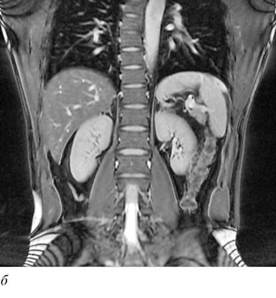

МРТ позволяет получать изображения в трех взаимно перпендикулярных проекциях - поперечной (аксиальной), фронтальной (корональной) и сагиттальной, а также в косых (наклонных) проекциях(рис. 4.38, 4.39).

Рис. 4.38. МРТ почек в норме: а - аксиальная проекция; б - фронтальная проекция